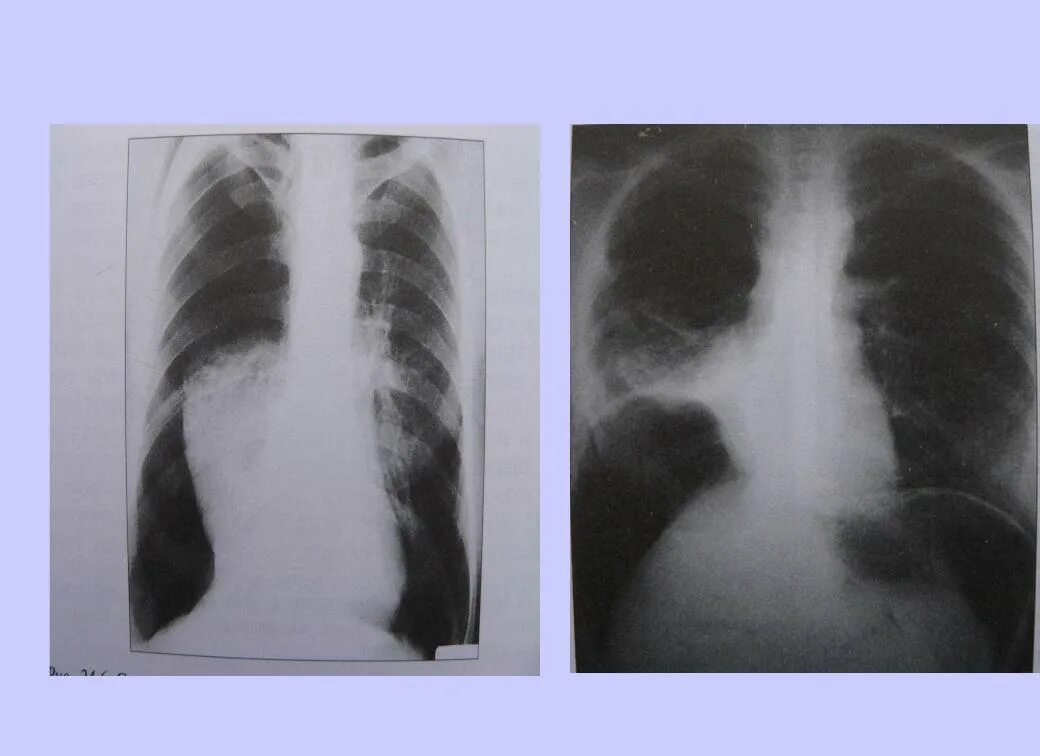

Коллапсотерапия при туберкулезе